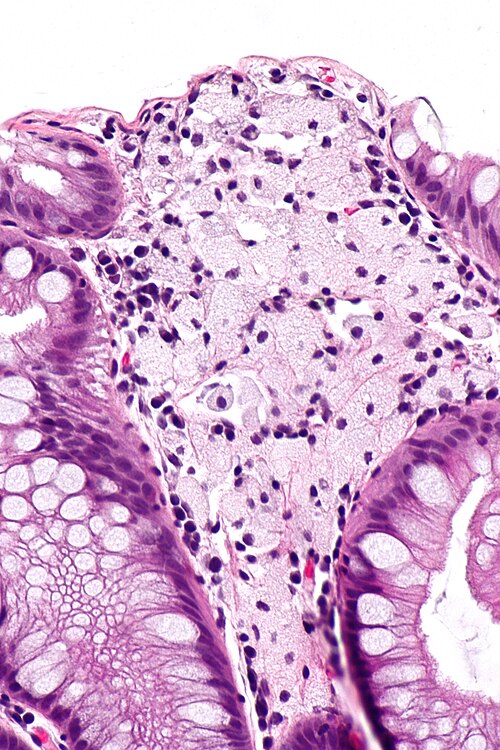

High magnification

High magnification. H&E stain.

Small benign appearing polyp.

Unusual. Looks benign.